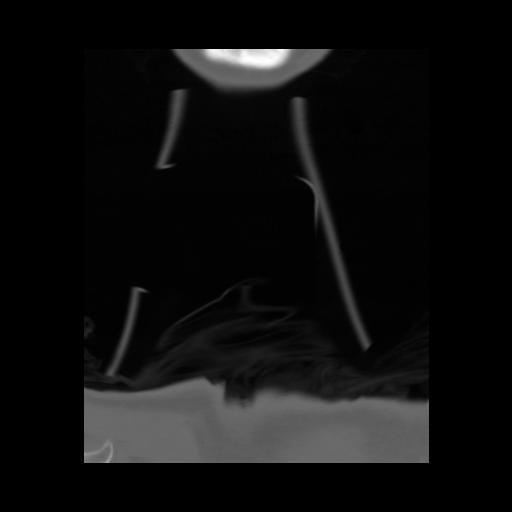

13 P.BLANDAS,,Coronal,2.000,P.BLANDAS,Coronal,